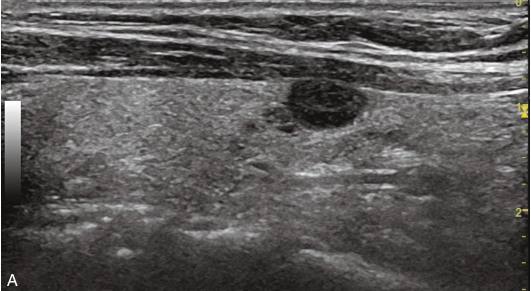

甲状腺左叶下极可见一低回声结节,大小约1.2cm×1.0cm×1.0cm,边界清楚,内未见强回声。CDFI显示甲状腺左叶下极结节内部及周边均未见血流信号,见图1-3-5。

图1-3-5 常规超声声像图

A.甲状腺左叶横切面超声图像;B.甲状腺左叶纵切面超声图像

甲状腺左叶下极结节超声造影全程呈整体无增强,病灶边界清楚,无增强面积等于灰阶超声所示,见图1-3-6、ER1-3-3。